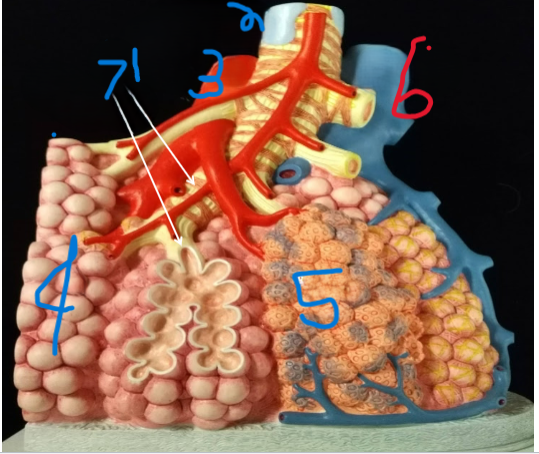

Terminal Bronchiole

What is depicted by #1

Bronchiole with smooth muscle

What is depicted by #2

Pulmonary vein, branch

What is depicted by #3

Alveoli

What is depicted by #4

Pulmonary capillaries

What is depicted by #5

Pulmonary artery, branch

What is depicted by #6

Respiratory Bronchiole

What is depicted by #7